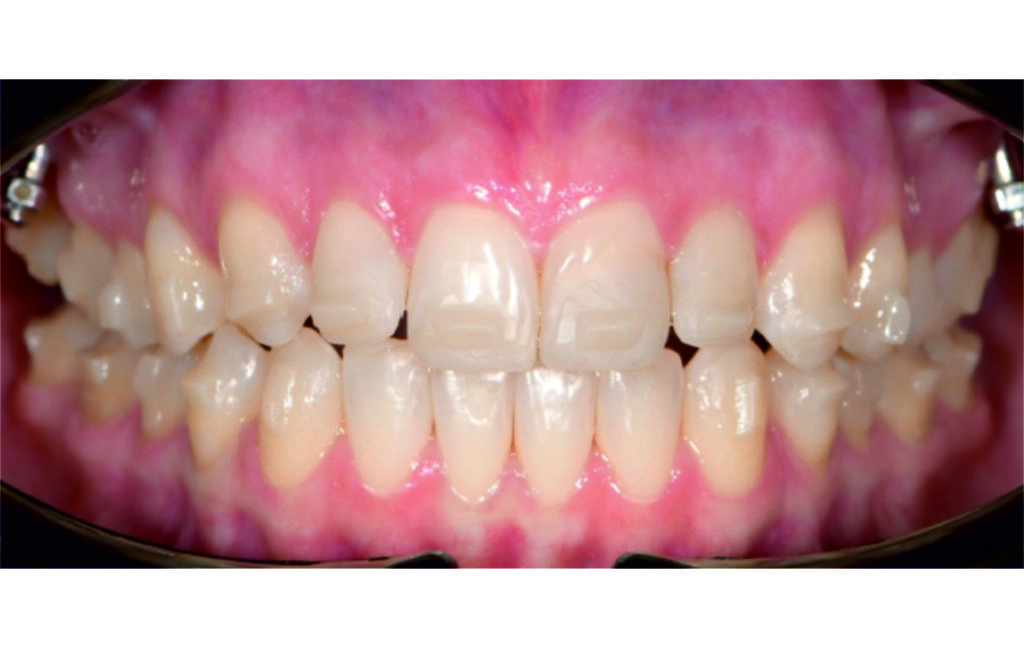

Angle Class II 2mm on the right, Angle Class II 2mm on the left, light mandibular asymmetry to the right, lower central line 1mm to the right, upper central line 1,5mm to the left, 1mm overjet and overbite. Sagittal asymmetry of upper dental arch. Light crowding upper and lower frontal segments, severe attrition of posterior teeth, night bruxism. Normal sagittal position of both jaws, high angle case, steep mandibular ramus,excessive lower facial height, open bite tendency.

The case initially presented as a moderate Class II on the right and a Class II tendency on the left, with tapered dental arches and an anterior open bite extending to tooth 26 in segment II.

A 1.5 mm deviation of the upper dental midline to the patient’s left was noted, along with a slight mandibular midline shift to the right, likely due to asymmetrical mandibular growth observed in the facial structure. Severe mesial rotations of teeth 16 and 26 were evident in the initial records. As derotation of 16, 26, 17, and 27 progressed up to aligner 16, the premolars in segments I and II moved distally, resulting in a bilateral Class I relationship, as intended in the initial treatment plan.

Derotation of 16 26 allowed Class II correction.